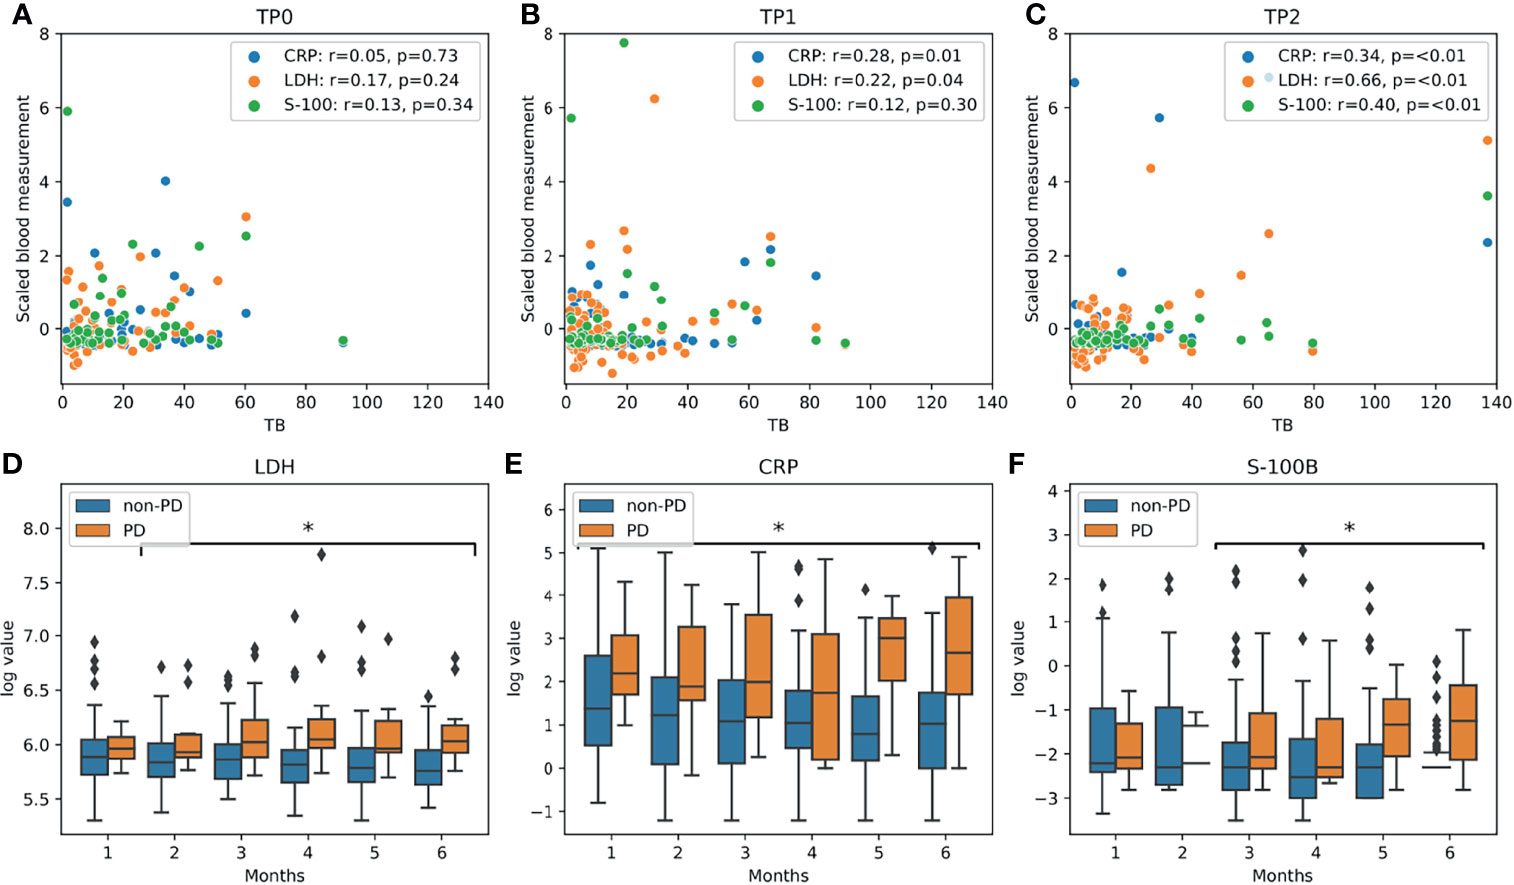

Improved Survival Prediction by Combining Radiological Imaging and S-100B Levels Into a Multivariate Model in Metastatic Melanoma Patients Treated With Immune Checkpoint Inhibition

We explored imaging and blood bio-markers for survival prediction in a cohort of patients with metastatic melanoma treated with immune checkpoint inhibition.

94 consecutive metastatic melanoma patients treated with immune checkpoint inhibition were included into this study. PET/CT imaging was available at baseline (Tp0), 3 months (Tp1) and 6 months (Tp2) after start of immunotherapy. Radiological response at Tp2 was evaluated using iRECIST. Total tumor burden (TB) at each time-point was measured and relative change of TB compared to baseline was calculated. LDH, CRP and S-100B were also analyzed. Cox proportional hazards model and logistic regression were used for survival analysis.

Our analysis shows only a weak correlation between LDH and TB. Additionally, baseline TB was not a prognostic factor in our cohort. A multivariate model combining early blood and imaging biomarkers achieved the best predictive power with regard to survival, outperforming iRECIST.